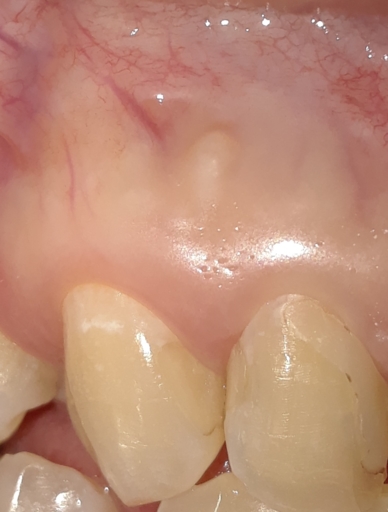

Root canal re-treatment- periapical cyst

Hi, I had a root canal re-treatment due to a periapical cyst. I had no symptoms but decided to be proactive. The doctor opened the canal and drained it. A week later the doctor disinfected the canal and filled it in. He didn't use calcium hydroxide...